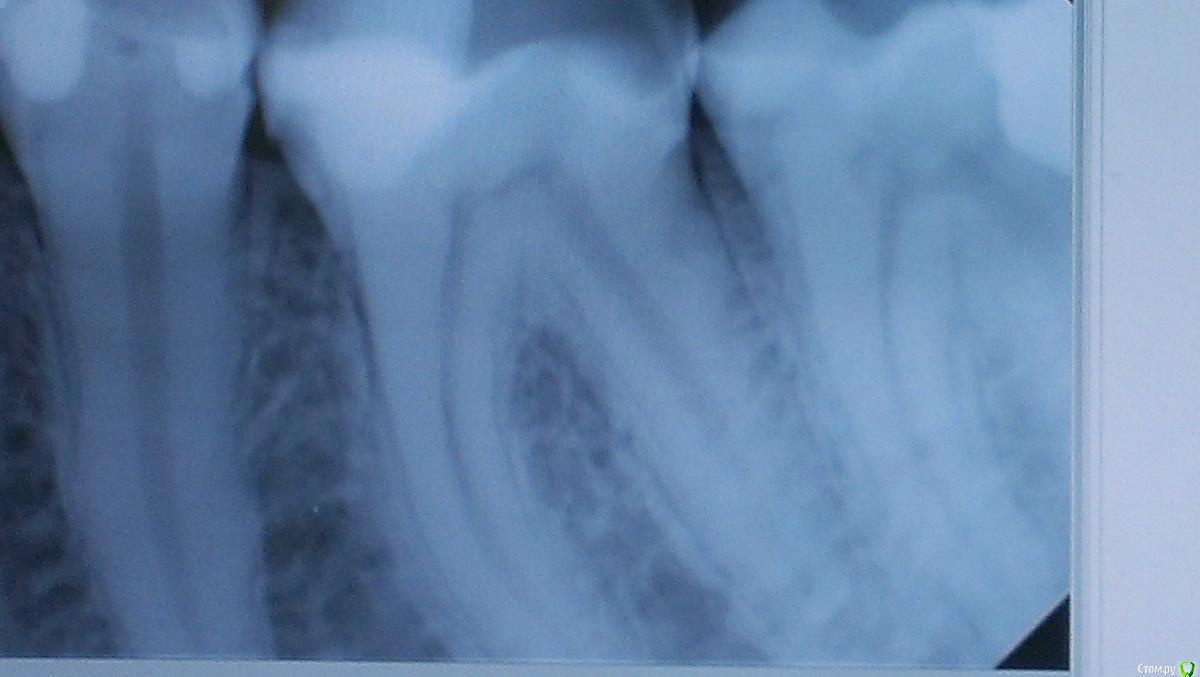

Girl Опубликовано 8 июня, 2015 Поделиться Опубликовано 8 июня, 2015 Обратилась пациентка с такой проблемой. Полгода назад на зуб 26 поставили коронку, при этом доктор подгонял ее по прикусу и стачивал зуб 36, пилил не по пломбе, а по зубу.Зуб болит при жевании, болеть начал сразу, то есть уже полгода ) дентин немного огален.Вопрос такой: достаточно будет поставить пломбу? Или нужно сразу депульпировать? Снимок прилагается. Ссылка на комментарий

young_and_beautiful Опубликовано 8 июня, 2015 Поделиться Опубликовано 8 июня, 2015 (изменено) Снимок нечеткий. Там с дистальной стороны полости нет? Но я не депульпировала бы. Можно попробовать вначале просто пломбу и понаблюдать. Изменено 8 июня, 2015 пользователем young_and_beautiful 1 Ссылка на комментарий

Girl Опубликовано 8 июня, 2015 Автор Поделиться Опубликовано 8 июня, 2015 Там с дистальной стороны полости нет? да, там есть полость...еще одна проблема. А пробы проводили? термометрия? Что под старой пломбой?пробы проводила, на холод - быстропроходящая реакция. Что под старой пломбой - не знаю, не вскрывала (пациентка не готова была лечиться), выглядит прилично вроде, без вторичн. изменений.Снимок нечеткий. Там с дистальной стороны полости нет? Но я не депульпировала бы. Можно попробовать вначале просто пломбу и понаблюдать.А вы бы прокладку ставили бы? И какую? А что с полостью на дистальной поверхности делать? Вскрыть и СИЦ залить? Ссылка на комментарий